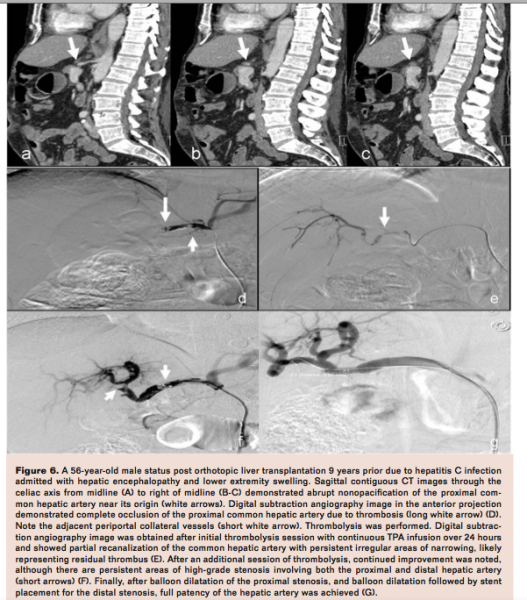

Hepatic Artery Thrombosis

Hepatic artery thrombosis (HAT) is the most common vascular complication after orthotopic liver transplantation, with an estimated incidence of between 4% and 11% in adult transplants and between 11% and 26% in the pediatric population.10-14 Patients with HAT have a 30% to 50% incidence of eventual liver failure, leading to retransplantation or death. Hence, maintaining hepatic artery patency is likely an important variable in minimizing graft loss and mortality.15 Clinically, patients will often present with elevated liver enzymes, biliary leak, cholangitis, or other signs of rejection.15 The first-line diagnostic imaging modality is DUS. A study by Vit et al found the presence of a tardus parvus waveform to be the most reliable individual indicator of hepatic artery stenosis (HAS) or HAT, with a sensitivity of 91% and specificity of 99.1%.16 Imaging features of hepatic artery thrombosis from underlying stenosis on DUS demonstrating parvus tardus spectral waveforms are seen in Figure 5. If Doppler US and/or CT is suspicious for HAT, the next step is typically an arteriogram to confirm imaging finding. Urgent thrombectomy and revascularization is currently considered the treatment of choice in cases of early diagnosis of HAT.17 Surgical thrombectomy or retransplantation may also be necessary in patients in which percutaneous techniques fail (Figure 5). In cases of very early diagnosis, selective thrombolytic therapy can be used to try to restore hepatic flow (Figures 5-6).2

Hepatic Artery Stenosis

Hepatic artery stenosis is seen in 5% to 11% of transplants and has up to a 65% chance of developing into HAT within 6 months.10 Most stenoses occur at or within a few centimeters of the arterial anatomosis.18 The biliary epithelium is perfused exclusively by the hepatic artery; as a result, disruption in flow as a result of a stenosis could result in hepatic artery thrombosis, hepatic infarction, biliary ischemia and necrosis, fulminant hepatic failure, sepsis, and bacteremia.3 HAS is typically diagnosed on DUS. One study by Rinaldi et al reported the sensitivity, specificity, positive predictive value, negative predictive value, and accuracy of DUS in diagnosing HAS to be 100%, 99.5%, 95%, 100%, and 99.5% respectively.3 These results were similar to two previous studies by Tamsel et al and Platt et al.19,20

Endovascular treatment of HAS can be performed with high technical success, acceptable morbidity, reduced invasiveness when compared to traditional surgical procedures, and similar overall rates of patient survival at 5 years when compared to traditional surgical procedures.10,21-25 The need for repeat intervention is common in our experience. Therefore, periodic follow-up imaging is routine at our institution. Initial use of a stent may improve patency when compared with percutaneous transluminal angioplasty. The not infrequently observed need for reintervention is illustrated in Figure 6 where subsequent session of thrombolysis and angioplasty were partially successful but only after stent placement achieved full patency. The efficacy of this approach was recently demonstrated in a series by Denys et al, where primary stent patency at 3, 6, and 12 months was 68%, 62%, and 53%, respectively, with a standard deviation of 14% for a confidence interval of 95%. Moreover, secondary stent patency at 3, 6, and 12 months was 84%, 77%, and 60%, respectively, with a standard deviation of 22%. The authors noted that only 4 of the 13 total patients in the series had developed restenosis at 1 year.22 Therefore, in many cases primary stent placement has become an increasingly attractive option at our institution vs balloon angioplasty alone.